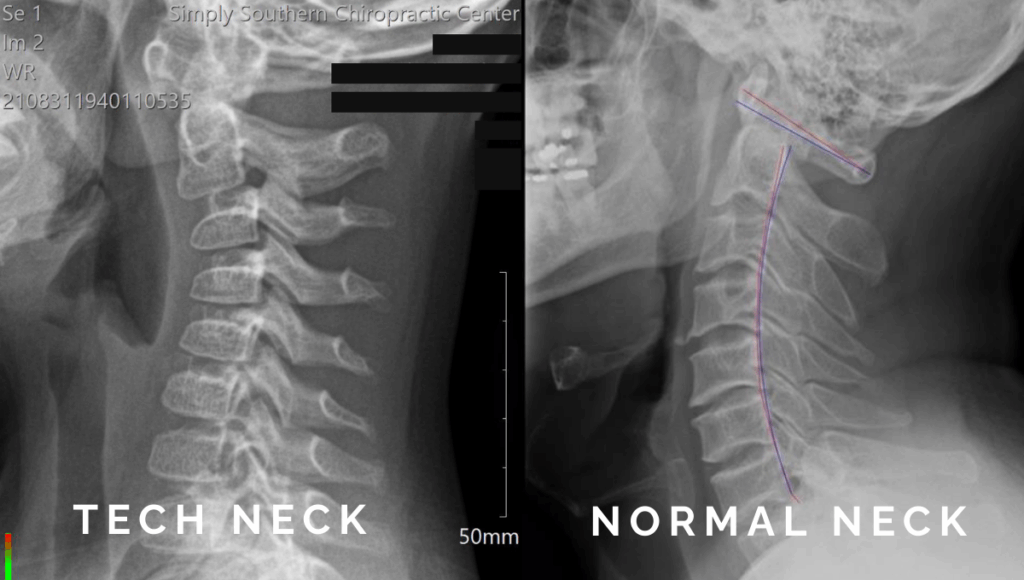

When your head tilts forward (like when you check your phone or work on your laptop), it puts extra weight and pressure on the spine. Instead of your neck carrying the normal load of about 10โ12 pounds, the strain can jump to 40 pounds or more, depending on the angle. Thatโs a lot of extra weight! Over time, that stress can:

- Flatten the natural curve of your neck, making it harder for your spine to do its job.